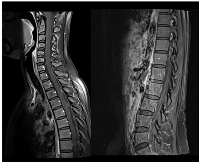

Figure 2

Neuraxis MRI at BM and LMC initial moment of diagnosis.

Disseminated LMC (extended to cerebellar fissures, midbrain, brachiocephalic bridge and cranial nerves emergence).

Figure 4

CE and neuraxis MRI response evaluation after 3 cycles of T-DXd.

LMC was noticeably reduced (in extension and intensity).

Sixteen months later (1.3 years), the patient was admitted to the emergency department with severe right headache (only mild response to pain medication and presence of other red flags: vomiting, night awakening, neurological deficits - visual deficits, facial paresthesias, dizziness; vertigo and decreased left upper limb muscular strength). Cranioencephalic computed tomography (CE-CT) showed a heterogeneous space-occupying lesion, in the right posterior parietal-parasagittal cortico-subcortical area, with vasogenic edema and sulcal effacement, compatible with a new BM lesion. Cranioencephalic magnetic resonance imaging (CE-MRI) confirmed the lesion genesis, showing new pachymeningeal carcinomatosis (right next to the lesion) and disseminated leptomeningeal carcinomatosis (LMC) (extended to cerebellar fissures, midbrain and brachiocephalic bridge, involving the cranial nerves emergence as well) (Figure 1). An important mass effect was present, compressing and occluding the right vertebral artery V4 terminal segment. Neuraxis MRI confirmed disseminated LMC in all neuraxis (extension to the conus medullaris limit) (Figure 2). Lumbar puncture showed a turbid cerebrospinal fluid (CSF), with cytology demonstrating small, scattered lymphocytes, large epithelial cells exhibiting irregular, hyperchromatic nuclei, and the presence of the ‘cell-in-cell’ phenomenon. The fluid was histologically confirmed as central nervous system (CNS) metastasis of HER2 positive BC. Re-staging showed neither local nor distant disease.

A slow but steady neurological improvement was achieved, with full autonomy recovery after only three cycles of T-DXd. Response evaluation with CE and neuraxis MRI showed excellent disease response: right parietal lesion was residual and pachymeningeal infiltration was not found; LMC was noticeably reduced (in extension and intensity) (Figures 3 and 4). Toraco-abdominal and pelvic CT (TAP-CT) was systematically negative for new distant secondary disease.